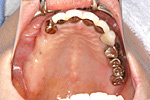

症例 6

① 虫歯でぼろぼろの歯は抜きます。

② 歯の無いところはインプラントで補います。

60才代 女性

総額:300万円(税別)

治療期間:1年6ヵ月

リスク副作用:清掃不良ですと歯周痛が再発します。セラミックが欠けることがあります。